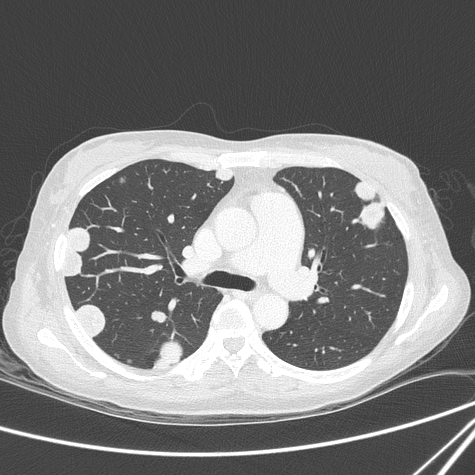

Пример: объемное образование левого легкого — гамартома. Кальцинация в виде «попкорна».